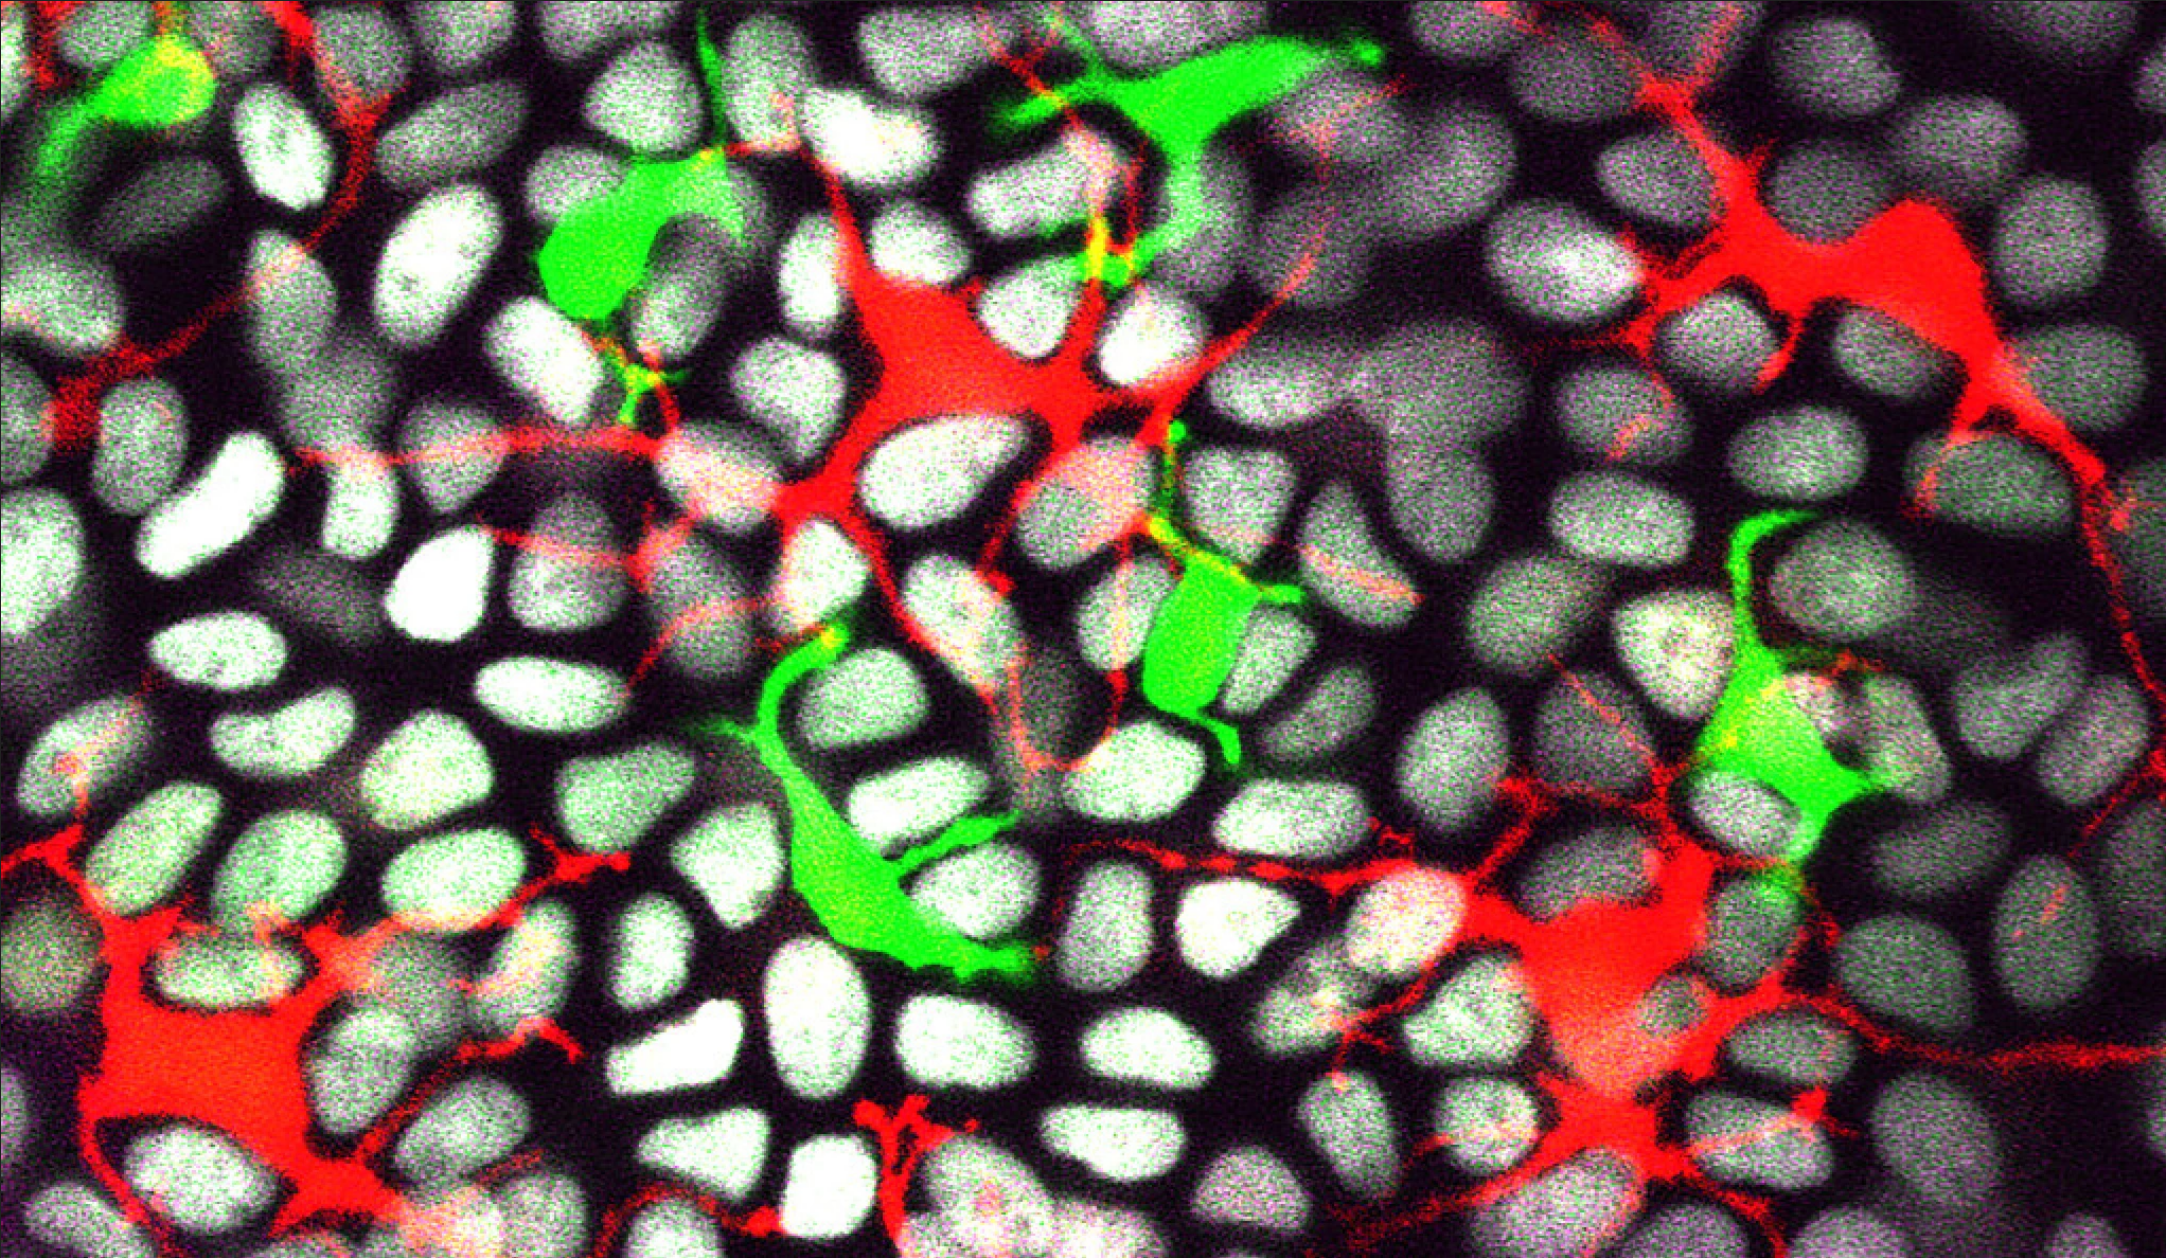

在这项新研究中,来自耶鲁大学和密歇根州立大学的研究人员研究了两种免疫细胞--朗格汉斯细胞和树突状表皮T细胞(DETC)--是如何跟周围的皮肤细胞或上皮细胞相互作用以维持这一屏障的。

果然,当科学家们敲除这种基因时,他们发现细胞的分布被打断了。基于这些实验以及免疫系统细胞跟上皮细胞相互作用的图像,研究人员得出结论,这两种类型的免疫细胞的分布模式是由Rac1基因和它们周围上皮细胞的密度调节的。